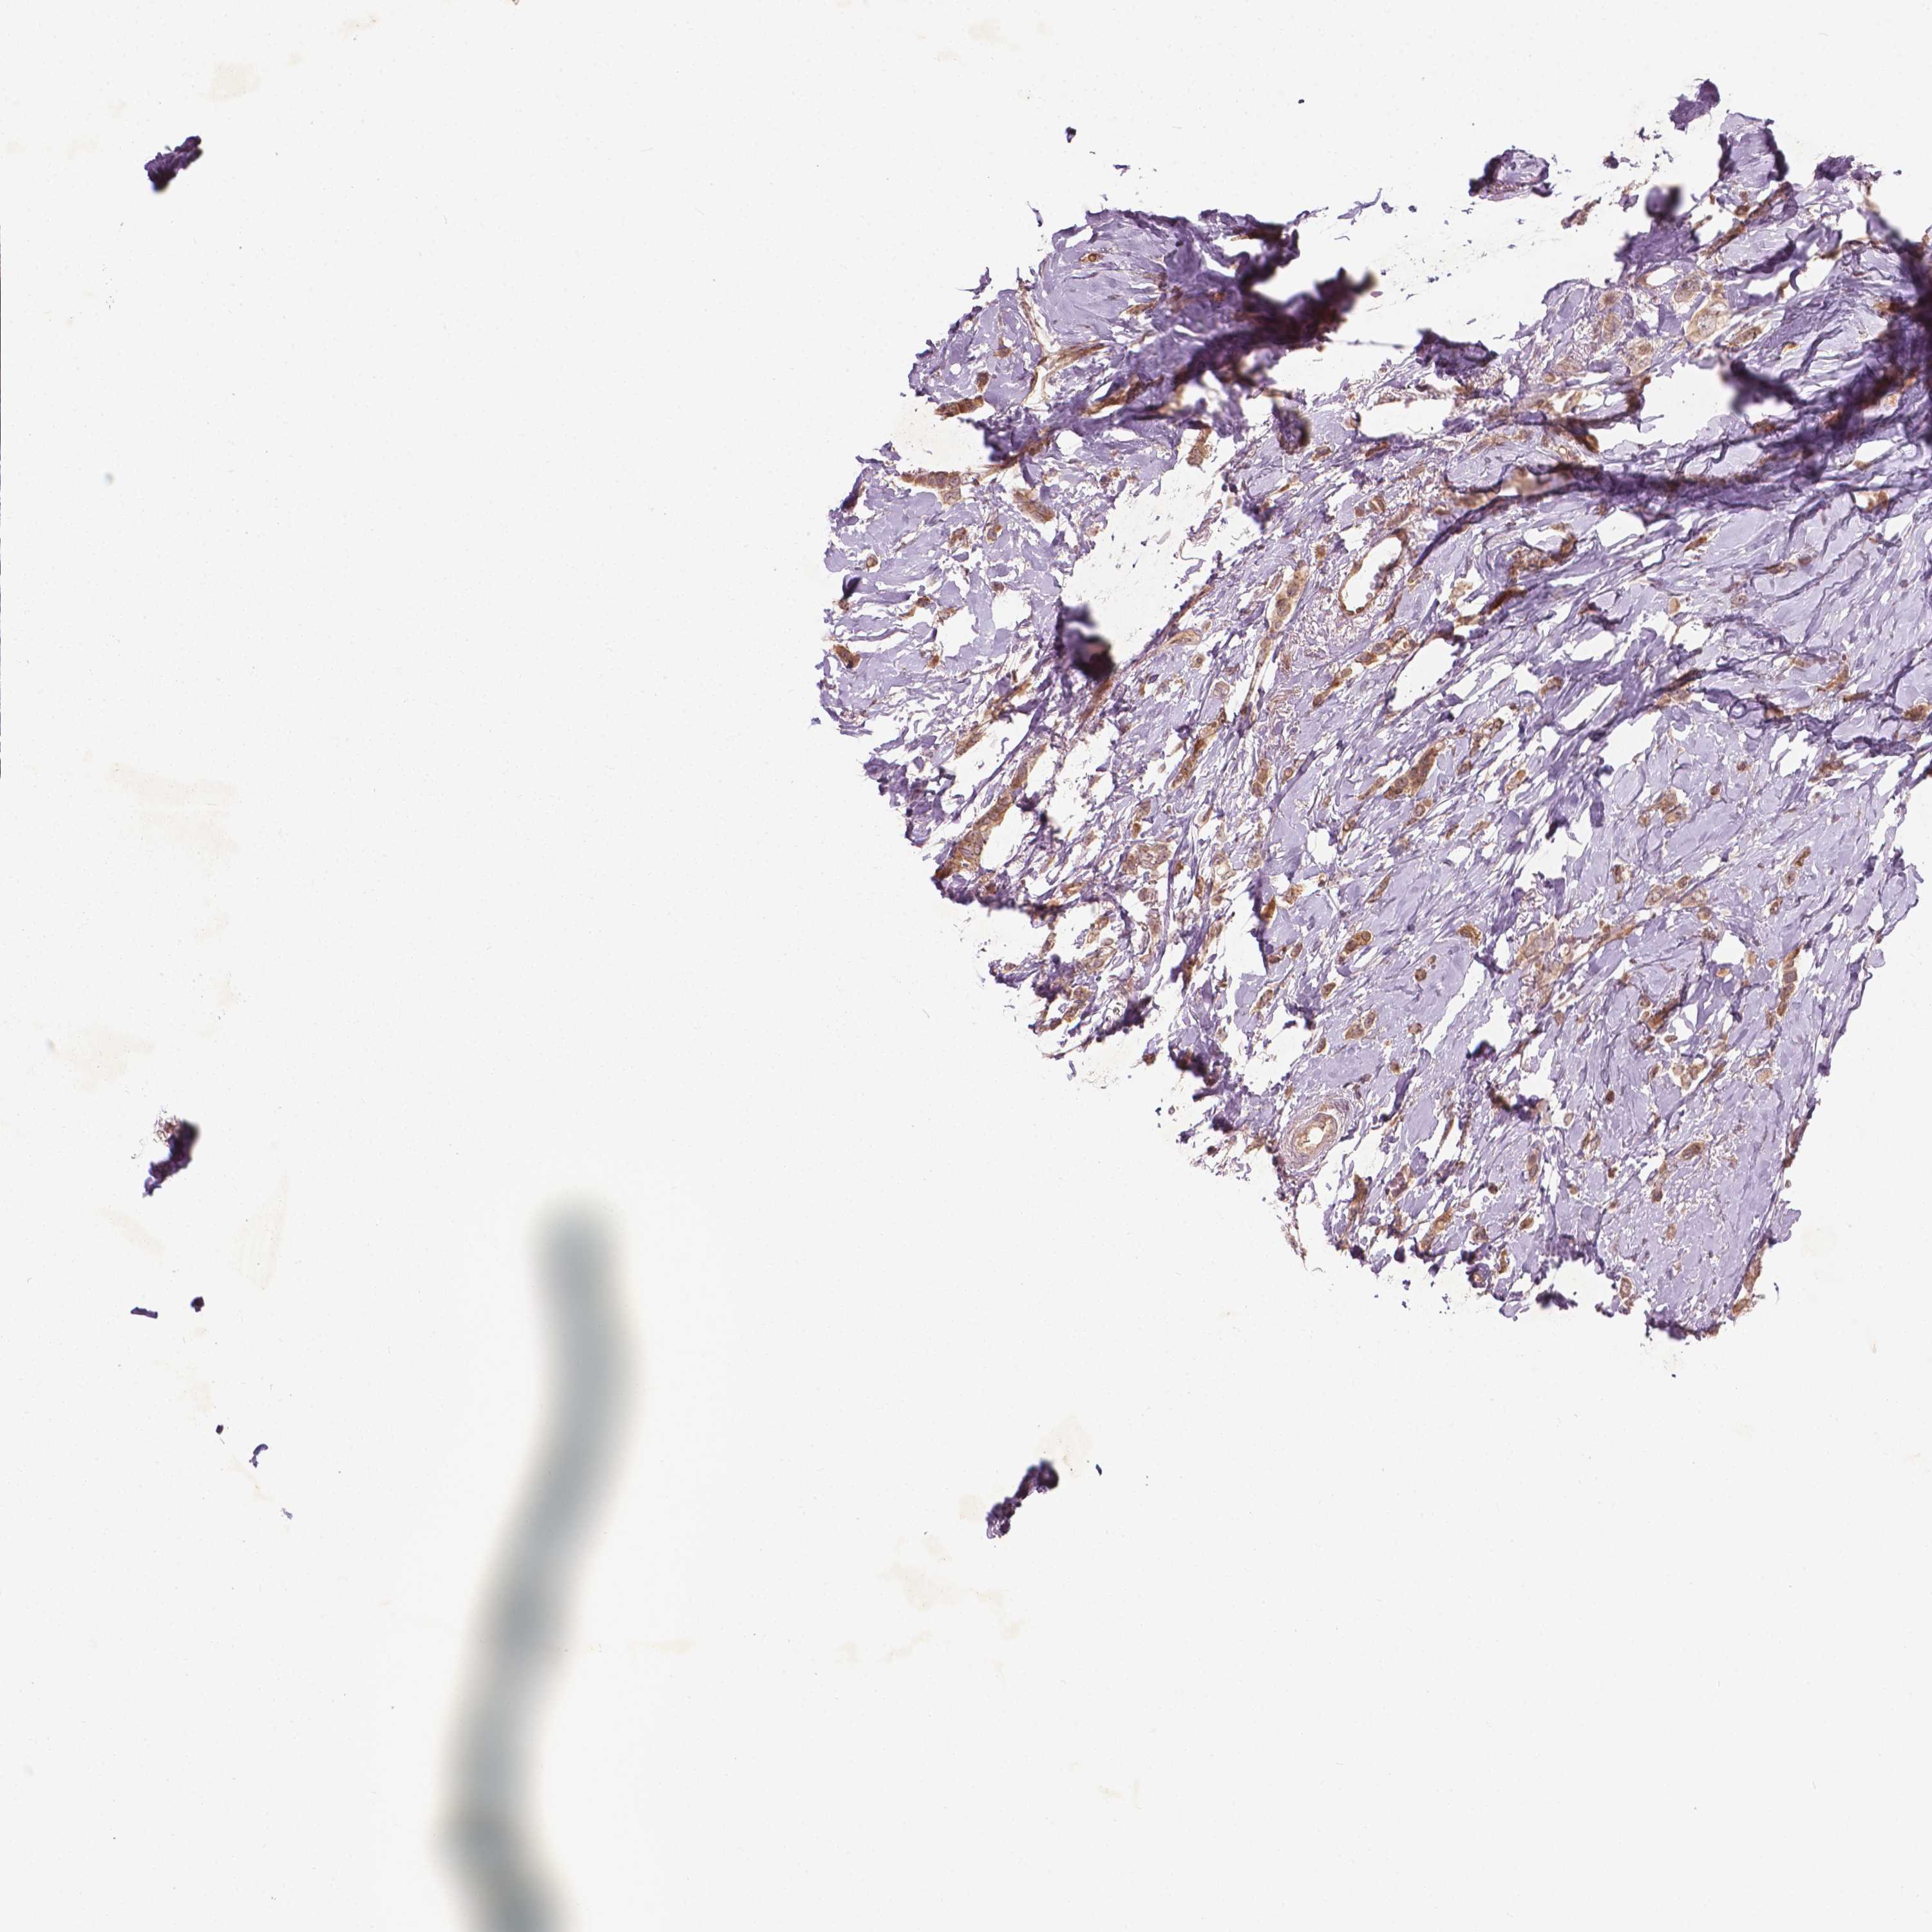

CANCER BREAST CANCER Show tissue menu

BRCA TCGA BRCA VALIDATION PROTEIN EXPRESSION